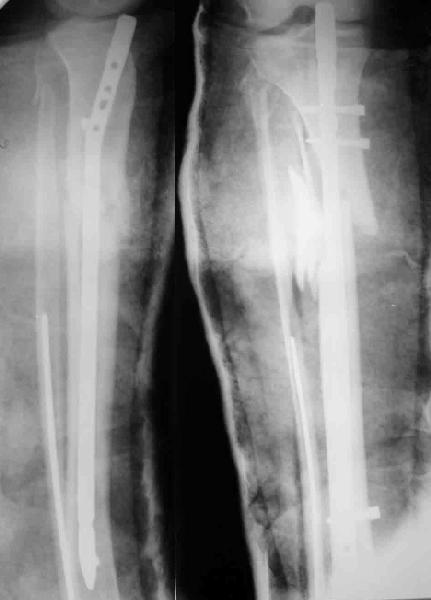

Декабрь 2003 22 июня 2004

В декабре прошлого года обсуждался случай бамперного перелома голени, когда молодой женщине в одной из больниц Москвы неудачно был выполнен остеосинтез гвоздем - это обсуждение можно просмотреть здесь, снимок тогдашний прилагаю.

Вчера поступила к нам в отделение. Клинически определяется приличная подвижность, градусов 35 в переднезаднем направлении. На снимках еще видны фиксированная тоникм стержнем уже сросшаяся малоберцовая кость, и тоже сросшийя перелом дистального метадиафиза большеберцовой кости без признаков хирургической фиксации (?). Сегодняшний снимок также в приложении.

Планируем удаление пластинки и закрытый интрамедуллярный остеосинтез с рассверливанием.